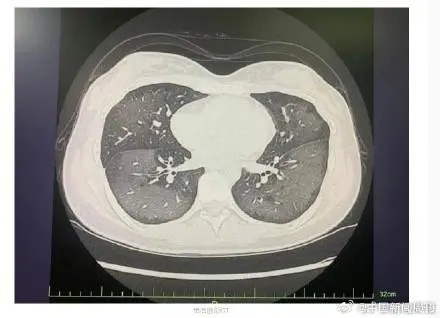

急诊科童娅玲主治医生经CT检查发现,丽丽的双肺呈现大范围白色样病变,报告提示“白肺”。丽丽被诊断为“急性过敏性肺炎”,于是对她给予吸氧、激素抗炎抗过敏等对症方法处理后,急性症状得到缓解,将她收入呼吸内科病房进一步住院治疗。

急诊科主任陆远强主任医生解释,“白肺”与使用防晒喷雾时吸入的有害物质有关,喷雾中的某些化学成分会刺激诱发一系列过敏反应,从而导致广泛的气管、支气管乃至肺水肿,让肺部无法正常工作。